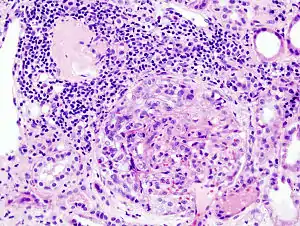

| MPO-ANCA阳性的急进性肾小球肾炎患者身上的新月体性肾小球肾炎组织病理学影像。切片经过苏木精和曙红染色。 | |

为新月体性肾小球肾炎。

- 镜下观:超过50%的肾小球球囊内有新月体形成。